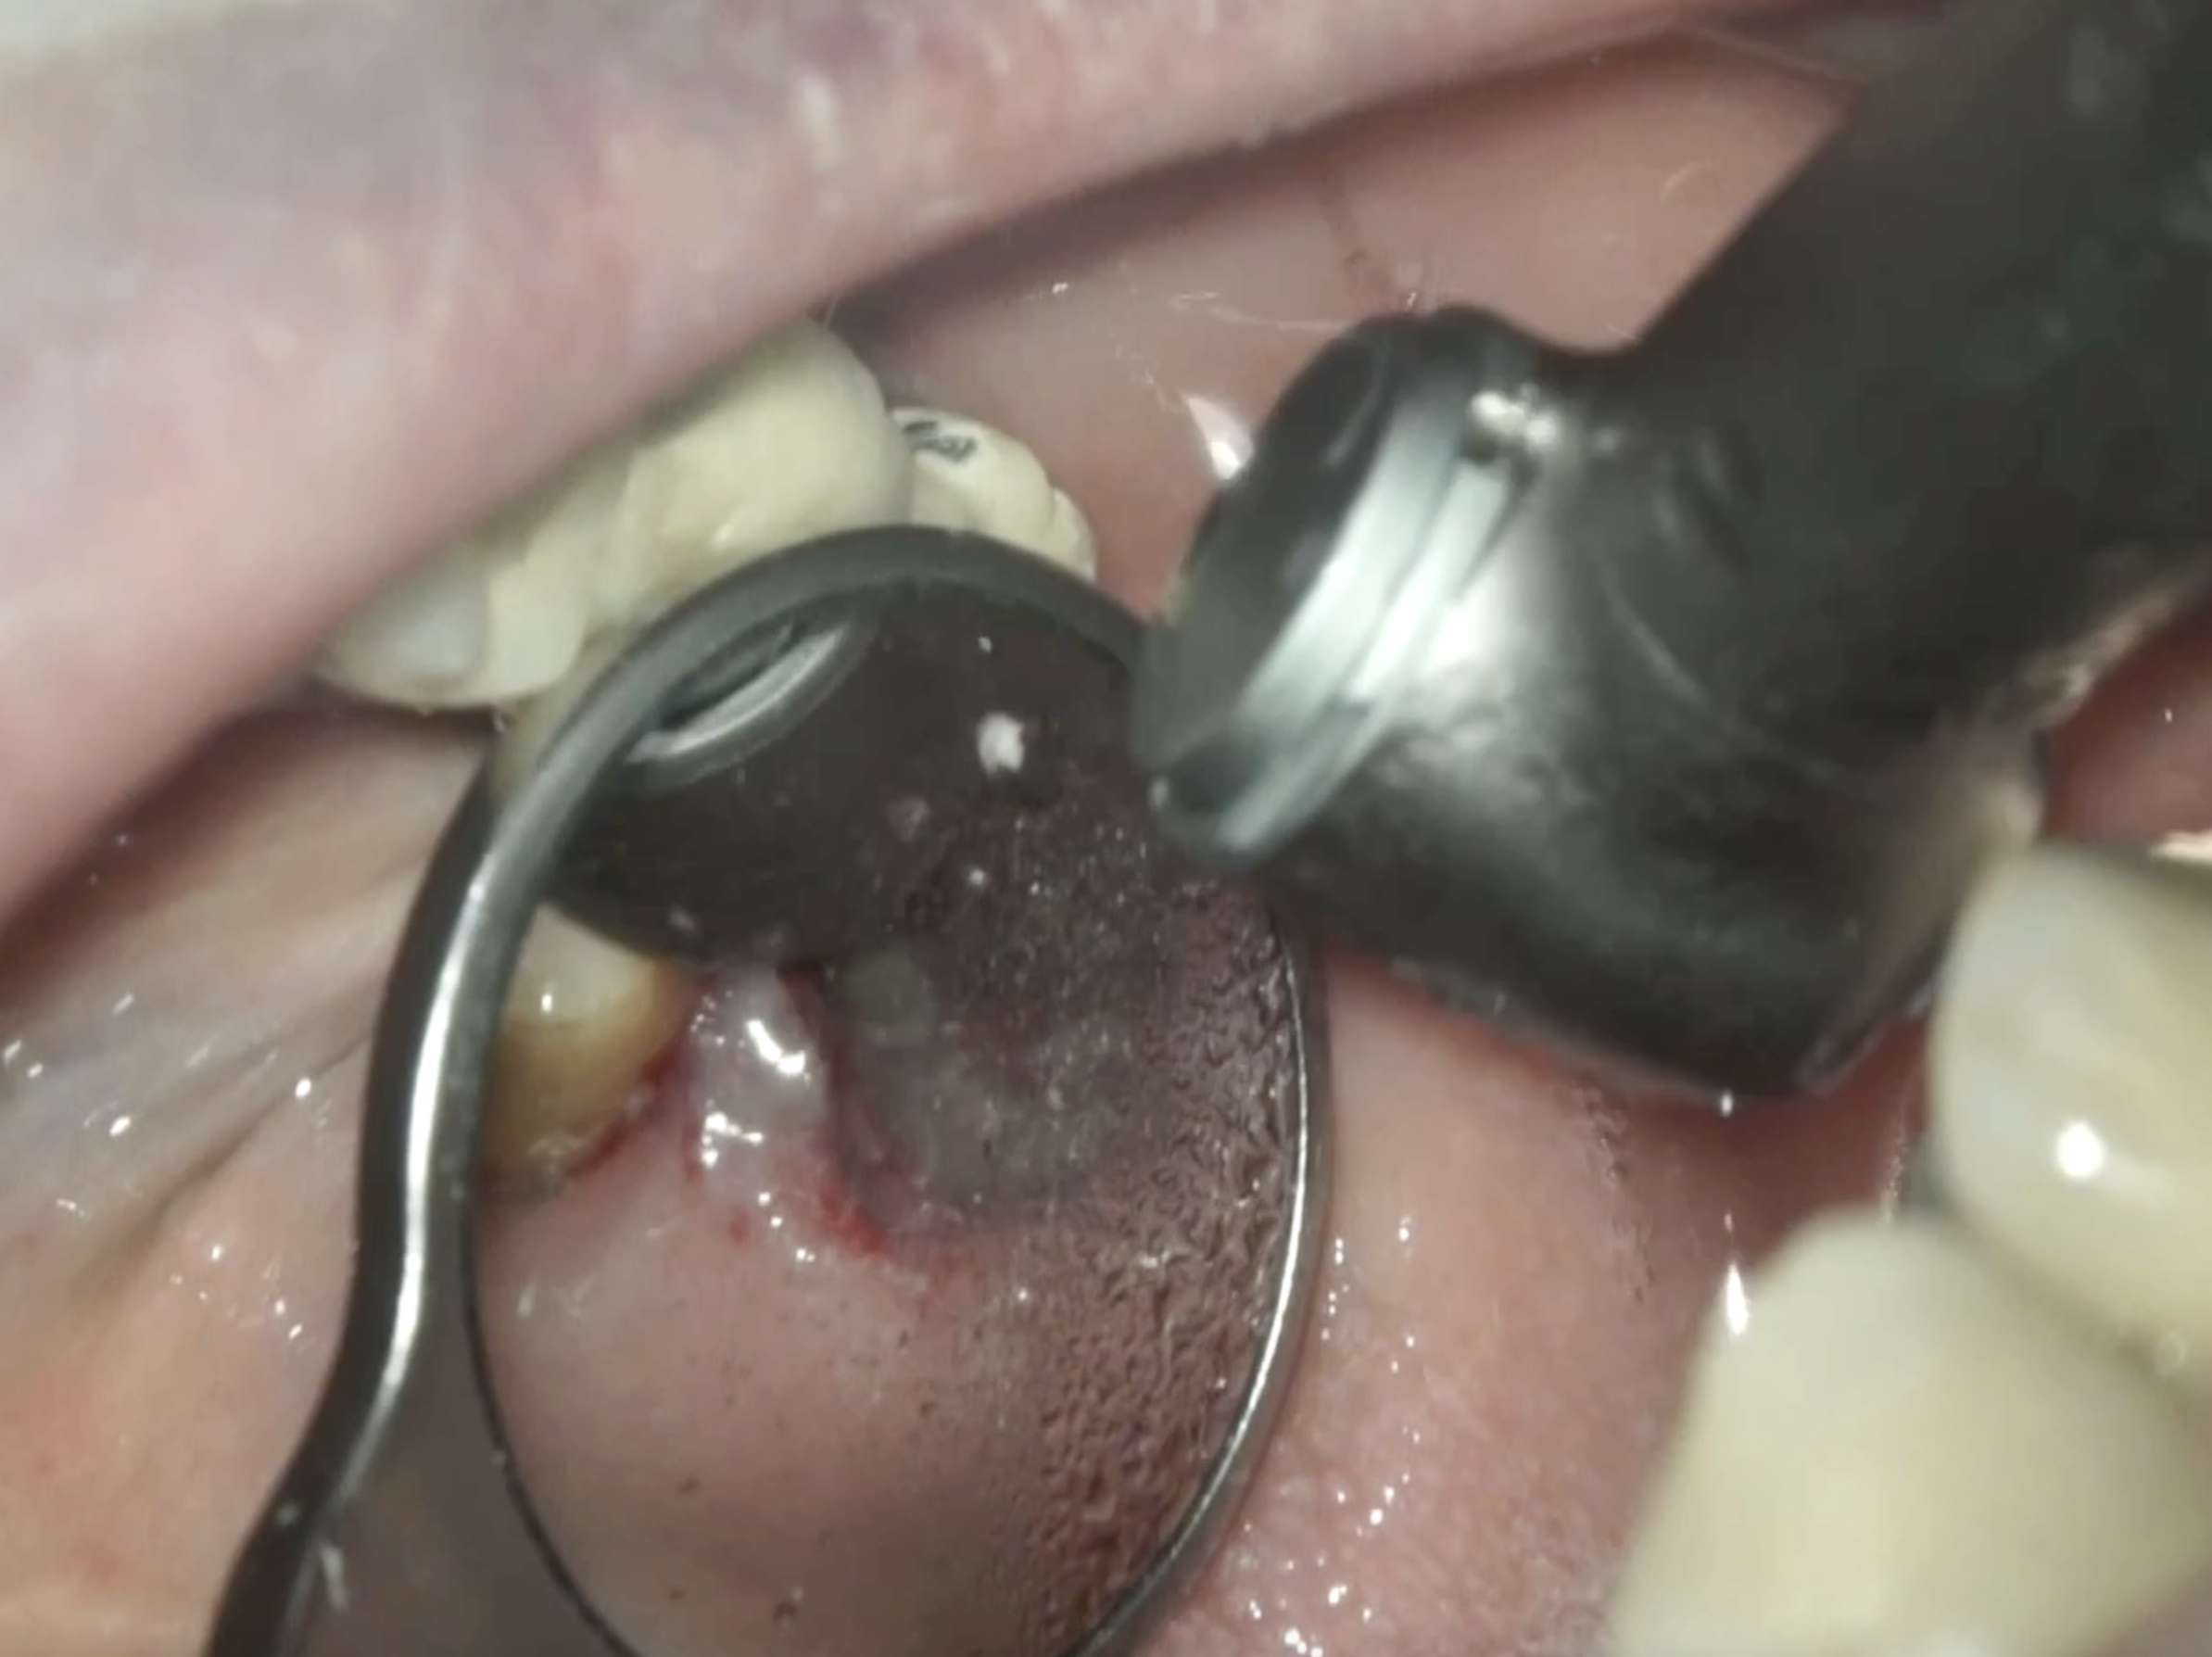

#2 Intentional Replantation(2025.7.15)

ラクスエータープラスで脱臼させて抜歯している。

口腔外でこの後は作業である。

メチレンブルーを使用して破折線がないか?精査した。

破折線はないようだ。

次に根切した。

この際の注意点は3mmも切断すると歯根がかなり短くなるため、1~2mm切断した。

その際に注意すべきはなるべく平行に切断するという必要がある。

当該部位(メチレンブルーで青く染色された部分)を逆根管形成し、逆根管充填した。